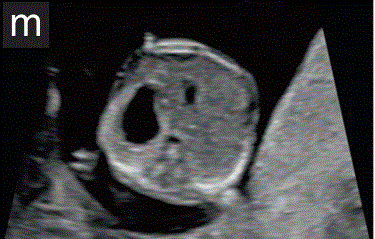

7.1.1胃和膀胱是腹部和骨盆中唯一的充满液体的回声结构。胃在腹部左侧的位置,连同左位心,有助于确定正常的内脏位置(图2m)。

图2 11+0至14+0周时,可作为详细胎儿超声检查的一部分获得的解剖图。

(m)胎儿腹部在胃水平处的横断切面。注意在左象限有充满液体的胃,以及胎儿肝脏和肋骨的正常外观和位置。